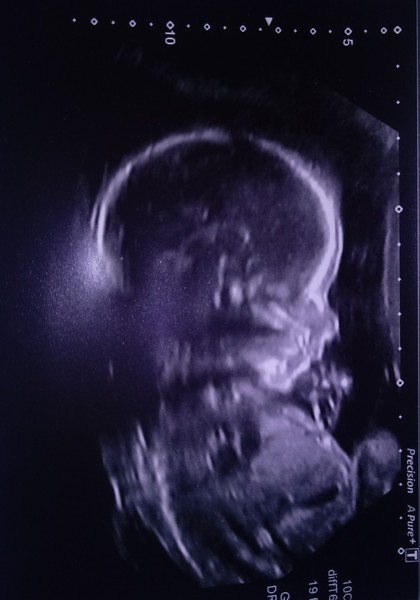

Here's my little teddy bear! Was a little pain in the hip and wouldn't move from his comfy spot no matter how much wiggling and jumping around I did 😔 had three separate scans with walk about time in between to try and get him to move... Managed to get everything in the end, only took about an hour 😂 still a boy and still on track for 23rd April!

Lovely pic MissYeti he must be well comfy where he is! Glad they got all the measurements they needed this time.

Aww @MissYeti such a sweet scan pic!

Teddy measured on the 17th centile for head circumference, every other measurement is between 37-42% Which seems more normal so I'm sort of worried he's going to have a small head!! Also he's currently presenting breech, how long does he have to make it into the head down position and stay there??